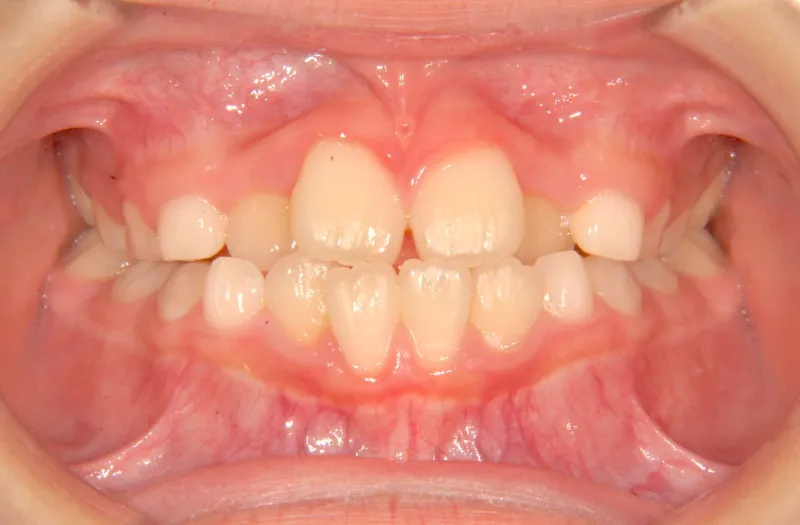

初診時年齢 小学校3年生 (男性) 主訴 前歯の噛み合わせが悪い

診断名 切端咬合 装置名

状態 永久歯が生える隙間がない(叢生)

受け口(下顎前突/反対咬合)

切端咬合

上の歯も下の歯も歯が生えるスペースが少ない為ガタガタしています。

前歯同士が上下で付き合わせる様に噛み(切端咬合)、

その横の歯は上の歯が下の歯の後ろにきて噛んでいる状態です(反対咬合)